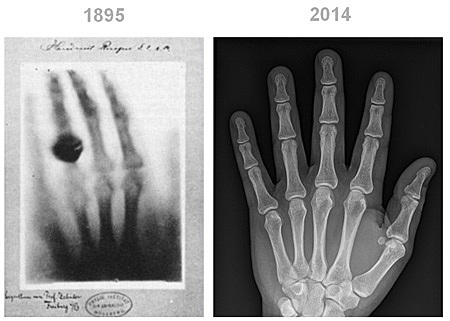

• The X-Ray

The X-Ray

Wilhelm Conrad was the first to discover the x-ray